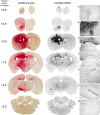

Neurogenetic disorders typically affect cells throughout the brain. Adeno-associated virus (AAV) vector-mediated transfer of a normal cDNA can correct the metabolic defects at the site of injection, but treatment of the entire brain requires widespread delivery of the normal gene and/or protein. Current methods require multiple injections for widespread distribution. However, some AAV vectors can be transported along neuronal pathways associated with the injected region. Thus, targeting widely dispersed systems in the CNS might be a pathway for gene dispersal from a limited number of sites. We tested this hypothesis in the ventral tegmental area (VTA), a region with numerous efferent and afferent projections. A single 1 mul injection resulted in transport of the vector genome to projection sites in distal parts of the brain. When compared with injections into the striatum, the VTA injection resulted in higher enzyme levels in more regions of the brain. The AAV-9 serotype vector was the most widely disseminated, but AAV-Rh.10 and AAV-1 were also transported after VTA injection. The effect on global lesions of a neurogenetic disease was tested in the mouse model of MPS VII (mucopolysaccharidosis VII), a lysosomal storage disorder. Widespread distribution of the vector genome after AAV-9 VTA injection resulted in even further distribution of the enzyme product, by secretion and uptake by surrounding cells, and complete correction of the storage lesions throughout the entire brain. This unprecedented level of correction from a single injection into the developed brain provides a potential strategy to correct a large volume of brain while minimizing the number of injections.